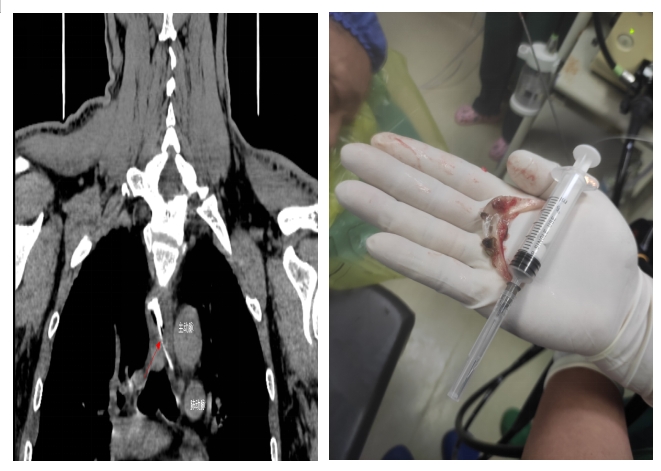

當(dāng)日,黃先生在家中與家人聚餐時,不小心被魚頭骨卡住,強行吞咽多次,出現(xiàn)食管與胸骨中上段后部疼痛,火速到衡陽市中心醫(yī)院就診。接診醫(yī)師對患者進行評估,嘗試經(jīng)喉鏡治療時,發(fā)現(xiàn)魚頭骨位置較深,行CT檢查發(fā)現(xiàn)魚頭骨卡于食管中段,穿破食管壁,與主動脈比鄰,非常危險,隨時威脅患者生命安全。隨即,患者被收治到心胸外科住院。入院后,廖金文主任一邊安慰,緩解患者的緊張情緒,一邊為其制定詳細的治療方案,計劃在手術(shù)室中嘗試胃鏡下取出魚刺。

在全身麻醉下,通過胃鏡,手術(shù)醫(yī)師清晰可見魚頭骨嵌頓部位為食管中上段。消化內(nèi)科副主任醫(yī)師劉昌智及主管護師羅雯娟攜手術(shù)室護理團隊,憑借豐富的臨床經(jīng)驗與技術(shù),10分鐘內(nèi)為患者實施了胃鏡取異物治療,成功取出魚頭骨,黃先生轉(zhuǎn)危為安。為防止意外,手術(shù)期間,心胸外科醫(yī)師在手術(shù)室全程守護。